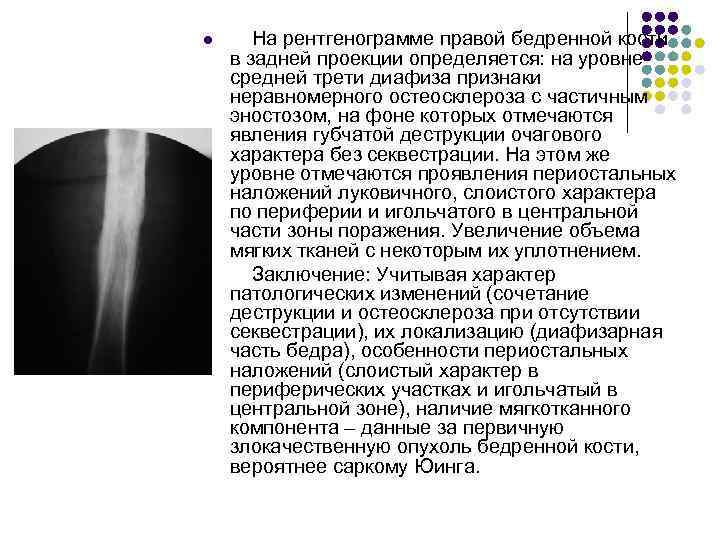

Вопрос: саркома Юинга это: l l l 1. Злокачественная опухоль из хондробластов 2. Злокачественная опухоль из остеобластов 3. Злокачественная опухоль из элементов костного мозга 4. Злокачественная опухоль из хондроцитов 5. Злокачественная опухоль из остеоцитов

Вопрос: саркома Юинга это: l l l 1. Злокачественная опухоль из хондробластов 2. Злокачественная опухоль из остеобластов 3. Злокачественная опухоль из элементов костного мозга 4. Злокачественная опухоль из хондроцитов 5. Злокачественная опухоль из остеоцитов

Ответ: l Злокачественная опухоль из элементов костного мозга

Ответ: l Злокачественная опухоль из элементов костного мозга